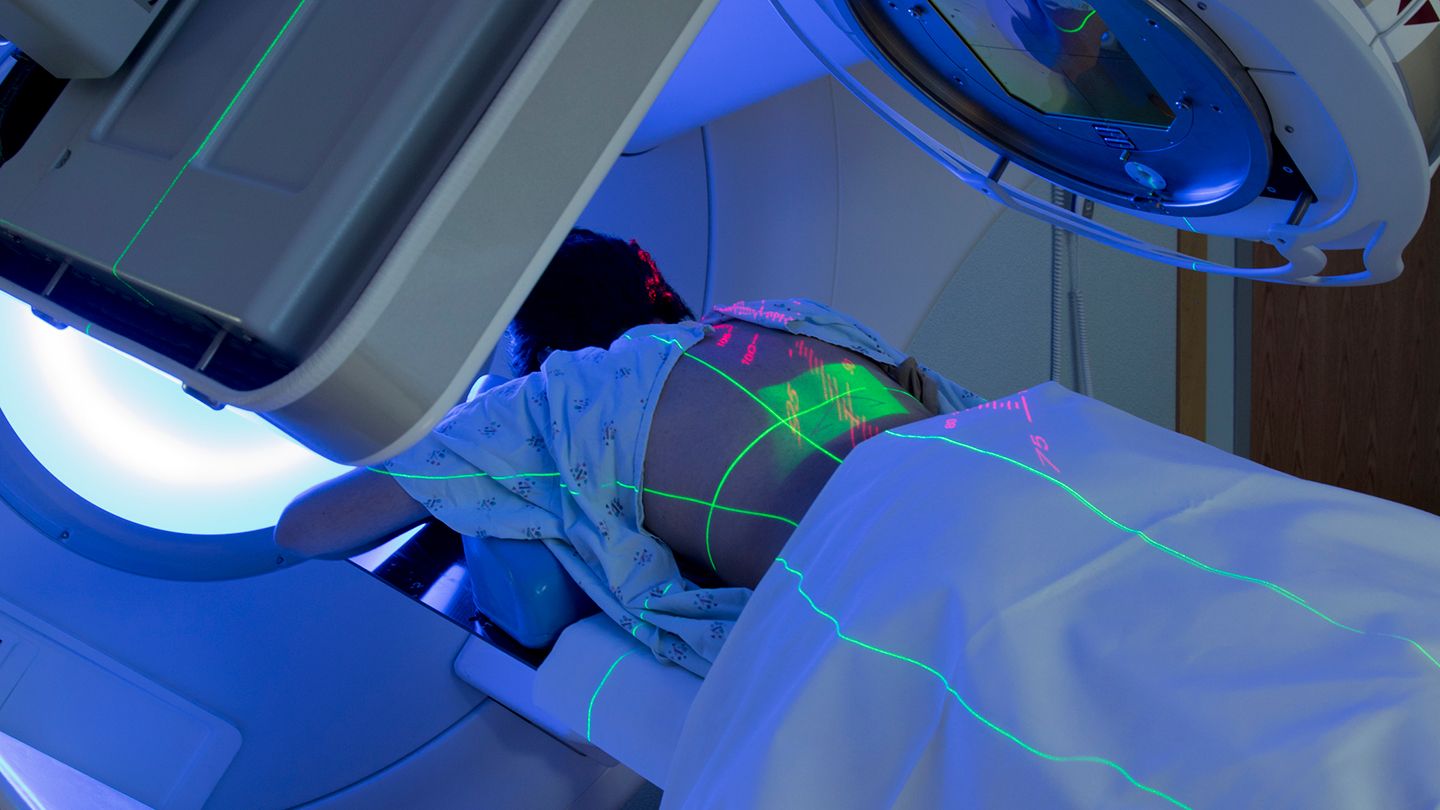

ტეგი: სხივური თერაპია